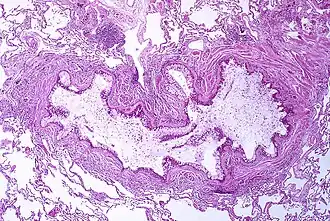

![]() Inflamación y obstrucción del bronquiolo por exudado mucoso característico del asma. | ||

Los cambios morfológicos vistos en el asma han sido descritos principalmente a partir de muestras de pacientes fallecidos por status asmaticus, es decir, un síndrome agudo de asma, sin embargo, parece que la histopatología en casos no mortales es muy similar.[5] Macroscópicamente, los pulmones se ven distendidos debido a una sobreinflación y pueden aparecer zonas con atelectasia. El hallazgo más notorio es la oclusión de los bronquios y bronquiolos por gruesos tapones de moco.

Bajo el microscopio, los tapones mucosos contienen espirales de células epiteliales formando los llamados espirales de Curschmann, que pueden habitualmente ser observados en el esputo de pacientes asmáticos.[33] Además, el moco contiene cristales de Charcot-Leyden y eosinófilos. Otra característica histológica del asma incluye un engrosamiento de la membrana basal del epitelio bronquial, edema y un infiltrado sobre las paredes bronquiales con prominencia de eosinófilos e hipertrofia del músculo de la pared bronquial así como de las glándulas submucosas, reflejando una broncoconstricción prolongada.[5]